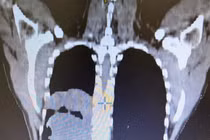

Bướu giáp thòng trung thất chiếm tỷ lệ nhỏ (3 – 20%) trong các trường hợp bướu giáp. Không chỉ xâm lấn hai thùy giáp, thực quản và khí quản, loại bướu này còn thòng xuống lồng ngực, chèn ép các mạch máu quan trọng...

Bướu giáp thòng trung thất là bệnh ít gặp, có một số trường hợp ác tính u xâm lấn hai thùy giáp, thực quản và khí quản, thòng xuống lồng ngực gây chèn ép các mạch máu quan trọng gây nguy hiểm tính mạng.

Bị bướu giáp trên 10 năm kèm tăng huyết áp, suy tim khiến bệnh nhân phải ngồi để thở, ăn uống nuốt nghẹn...Đặc biệt u giáp khổng lồ thòng xuống trung thất chèn ép máu, khí quản, thực quản...